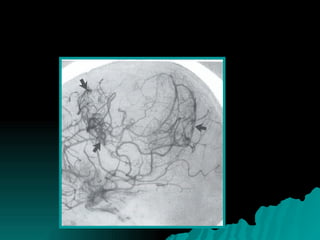

Este documento trata sobre los meningiomas. Los meningiomas son los tumores primarios extraaxiales más frecuentes del encéfalo. Generalmente ocurren en adultos y son más comunes en mujeres. La mayoría de los meningiomas son benignos, aunque también existen formas atípicas y anaplásicas. Los meningiomas se ubican principalmente en la región supratentorial y tienen características distintivas en imágenes como la TAC y la RM.